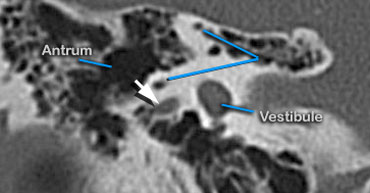

Antrum

At this level the antrum is seen surrounded by smaller mastoid aircells just lateral to the superior semicircular canals .

The three semicircular canals lie perpendicular to each other to sense acceleration and deceleration movements in each of the 3 spatial planes.

Static head position is sensed by the vestibule, which contains the position hair cells.

Different head positions produce different gravity effects by small calcium carbonate particles (otoliths) on these hair cells.

The antrum is a large aircell superior and posterior to the tympanic cavity and connected to the tympanic cavity via the aditus ad antrum.

It is surrounded by smaller mastoid aircells.